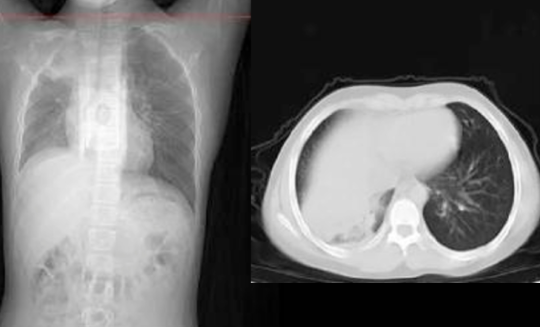

注意预防 秋冬季节本就是北美流感高发季节,但2023年冬天似乎有些不寻常,一种“白肺”疫情正在悄然蔓延,已经在美国爆发,引发一波儿童肺炎感染浪潮! 据外媒报道,美国有两个州现在儿童感染肺炎的病例正在激增,已经让医生们开始担心,这股疫情会扩散开来。 距离俄亥俄州辛辛那提郊外仅30英里的沃伦县,现在已经有142宗确诊“白肺综合症”的儿童病例,且一直在攀升,当地卫生官员表示这个数字已经“极高”。 多个学区都接连出现确诊病例,响起警报。 本周三,卫生官表示:“这不仅高于本地的平均水平,且符合俄亥俄州卫生部对疫情的定义。” 与此同时,马萨诸塞州西部还出现了大量“行走性肺炎”病例。 这个“行走性肺炎”是由细菌和病毒感染的混合物引起的,是一种比较温和的肺部疾病,患者会出现发烧和咳嗽的症状,但是没有痰。 ![]() ![]() 儿科医院的凯利医生接受采访时表示,现在正是呼吸道病毒 RSV 的流行季节,很多孩子患有上病毒性呼吸道感染、咳嗽、流鼻涕,还有一些发烧,对肺部也有影响。 ![]() 现阶段,80%患有“行走性肺炎”的儿童是由于首次感染RSV引起的,20%病例是由细菌引起的,可用抗生素治疗。 对于此波疫情,美国卫生当局也提出了几种可能性,其中之一就是大流行期间的封锁、戴口罩和关校一定程度上削弱了儿童的免疫力,使他们在疫后更容易患上季节性疾病。 康涅狄格州耶鲁大学医学院传染病专家斯科特·罗伯茨(Scott Roberts)博士表示,“这可能是已知病原体的复发,但由于孩子们对它们的免疫力低下,这些病原体的影响更大。” 这两个州目前的疫情都不是由新型病原体引起的,也不是所有的肺炎病例都是由同一感染引起的,而是几种季节性细菌和病毒的混合物同时袭击。 人们开始担心,这波肺炎蔓延,会让美国今年冬天可能爆发不堪重负的感染疫情。对此,CDC表示现在全国范围内尚未出现什么“不寻常”的数据。 除了这两个州,数据显示其他州的儿童肺炎水平遵循“季节性趋势”,没有任何异常情况,但CDC正在继续监测。 俄亥俄州卫生部门正在调查究竟是什么引发了疾病浪潮,疫情爆发的地区人口有200万左右,目前大部分患者都是儿童,平均年龄在8岁左右,有的孩子只有3岁。 ![]() 经检测,许多确诊儿童的肺炎支原体、链球菌和腺病毒检测都呈阳性。大多患者都有发烧、咳嗽、疲劳的症状,目前尚不清楚有没有出现死亡病例。 医生表示,大多数感染都是轻微的,但最近刚感染过呼吸道疾病的人面临更高的风险。 “(现阶段)我们不认为这是一种新型的呼吸道疾病,而是通常人们看到的肺炎,但病例数量正在大幅增加”。 随着假期的临近,大家都会回家团聚,与亲朋好友聚餐,卫生官也提醒所有人,需要采取必要的预防措施。“勤洗手,咳嗽时捂住口鼻,生病时待在家里,并及时接种疫苗。” 通常而言,细菌性呼吸道感染通常每隔几年就会爆发一次,肺炎支原体感染往往每三到七年就会达到顶峰。 只不过,2020年新冠疫情爆发以来,这种疾病还没有达到感染顶峰。 马萨诸塞州的医生表示,这次疫情的主要问题是呼吸道合胞病毒RSV,这是一种呼吸道病毒,每年导致10000多名美国人死亡,其中大多数是幼儿和老人。 “现在就是RSV的高发季节,我们看到了很多孩子患有上层病毒性呼吸道感染、咳嗽、流鼻涕、发烧,而RSV会导致下层病毒性呼吸道感染,传播到肺部。 ![]() 欧洲的荷兰和丹麦也正在经历类似的感染潮,“神秘”肺炎病例达到峰值。 秋冬本来就是各种呼吸道疾病的流行季节,年底了,各种聚会越来越多,希望大家都做好预防措施。 |